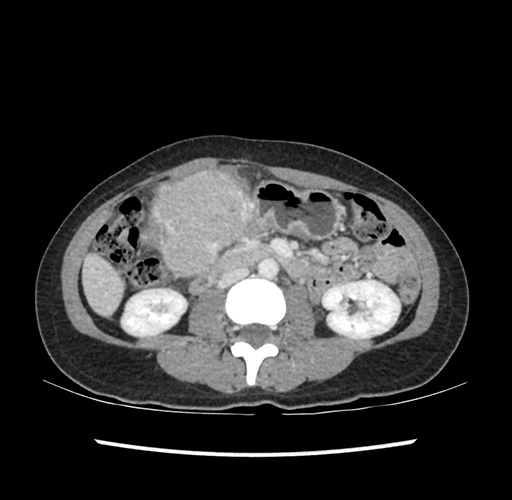

Imaging Analysis

Look through the patient's CT scan to identify any areas of concern for the necessary procedure.

Based on your CT findings, which issue(s) would give reason for "planned slowing down moment(s)" in this case?

Considering a standard left lateral sectionectomy procedure, what step(s) of the operation would you do differently in this case ?